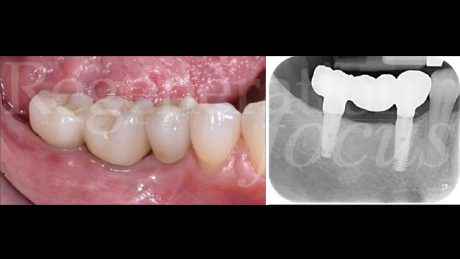

Una paziente di 44 anni, non fumatrice e in buone condizioni di salute generale, si è presentata riferendo significative difficoltà masticatorie, nel quarto quadrante, conseguenti alla perdita del ponte 45-47 per complicanze endodontico-protesiche. L’anamnesi medica non rivelava patologie sistemiche di rilievo né assunzione di farmaci che potessero interferire con i processi di guarigione ossea. L’esame intraorale evidenziava una discreta atrofia della cresta alveolare edentula con collasso vestibolo-linguale dei tessuti molli (Fig. 1). Gli elementi dentari adiacenti presentavano condizioni parodontali stabili. L’analisi radiografica tridimensionale, mediante CBCT, ha permesso una valutazione dettagliata del deficit osseo (Fig. 2). Dopo discussione delle diverse opzioni terapeutiche, inclusa la possibilità di impianti corti, si è optato per una rigenerazione ossea guidata mediante mesh customizzata.